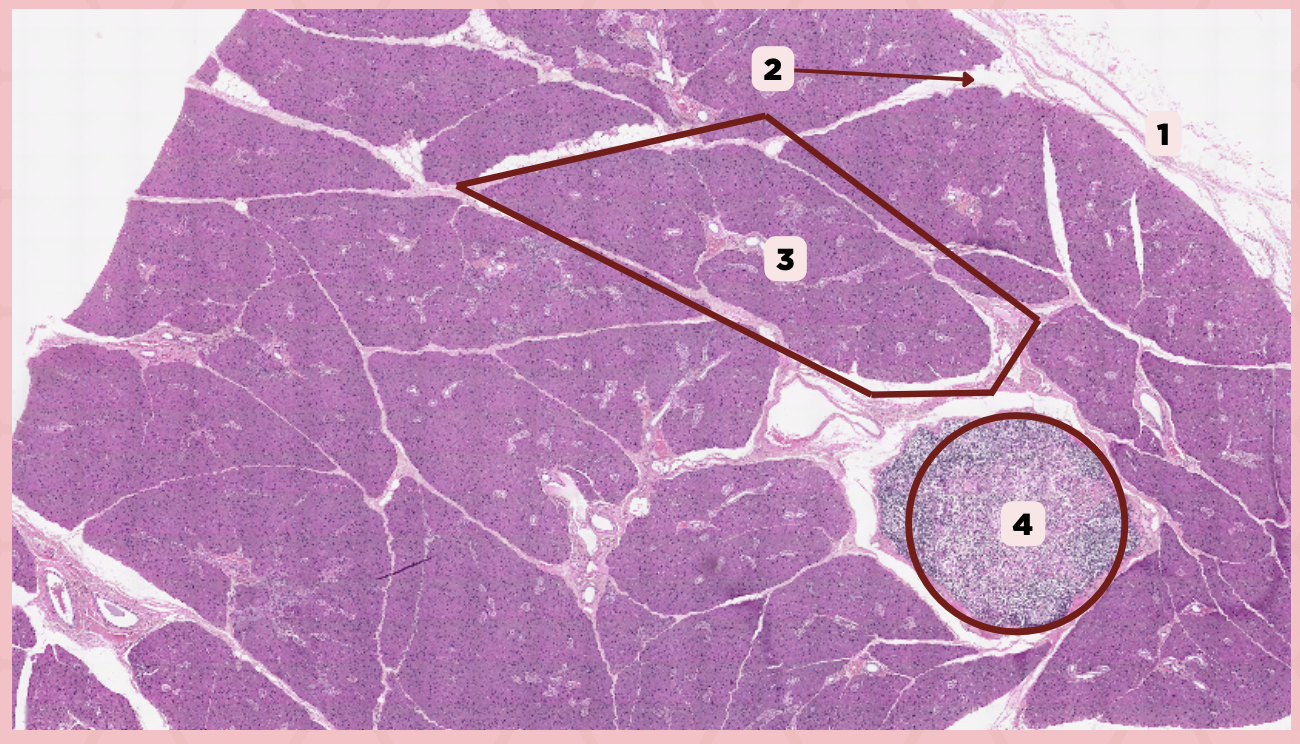

Parotid

Identify the specimen.

Capsule

Identify the structure labeled as 1.

Septa

Identify the structure labeled as 2.

Lobule

Identify the structure labeled as 3.

Lymph Node

Identify the structure labeled as 4.

C) Septa

Which of the following structures shown delineate the lobes and lobules of the parotid gland?

A) Capsule

B) Lobule

C) Septa

D) Lymph Nodes

A) Capsule

Which of the following structures encapsulates the parotid gland?

A) Capsule

B) Lobule

C) Septa

D) Lymph Nodes